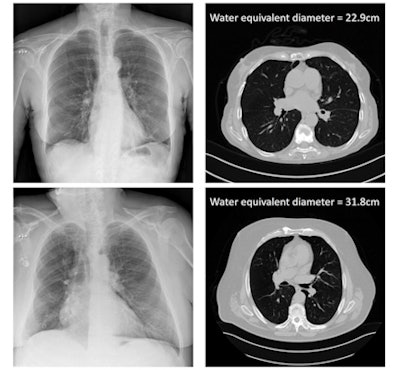

Bosmans and colleagues proposed an attenuation metric related to the dose absorbed in the patient -- based on the ratio of incident air kerma to detector air kerma -- that correlates with patient size. They defined this metric for both thoracic and abdominal projection radiography, using 137 thoracic and 137 abdominal projection images as input data. These patients also had recent CT exams of the same body part, serving as the gold standard for patient size.

To establish the ground-truth patient size, the researchers used the CT scans to calculate the water equivalent diameter (WED) and water equivalent thickness (WET) of all patients. They then plotted these ground-truth WED and WET values versus the natural log of the attenuation metric, for both thoracic and abdominal scans. This generated four correlation curves that could then be applied to estimate patient size based solely on DICOM information from the projection radiographs.